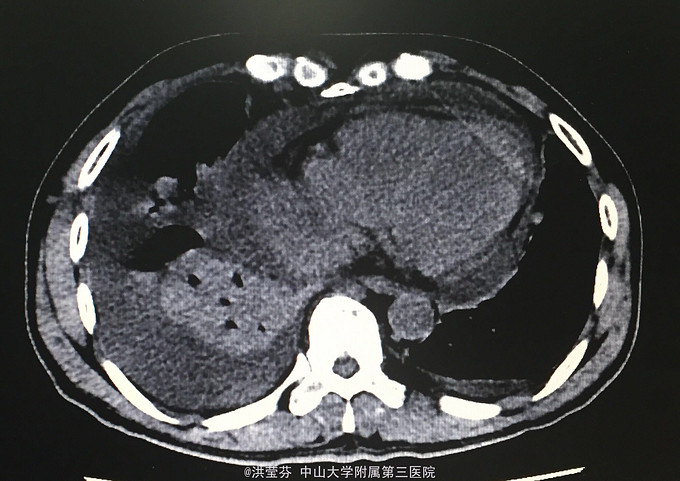

查体:KPS 60分,BSA 1.83m2,T 38.5℃,全身浅表淋巴结未触及明显肿大,胸壁可见浅表静脉曲张,呼吸急促,左下肺、右中下肺呼吸音明显减弱,其余肺野呼吸音促,可闻及少许实性啰音,心率110bpm,律齐,腹软,全腹无压痛、反跳痛,未扪及明显包块,肝脾肋下未触及,移动性浊音(——),肠鸣音正常,4次/分,双下肢无凹陷性水肿。 辅助检查:血常规无特殊,生化转氨酶稍升高,低钠低氯,CRP 227.9mg/L,凝血四项:Fib 8.14g/L。复查胸部CT提示:1.胸腺癌并纵膈淋巴结及双肺多发转移瘤,右心房、上腔静脉受侵并癌栓形成,病变较前进展。2.双肺炎症,以右肺为著。3.双侧胸腔及心包积液。上腹部CT提示:1.下腔静脉早显并肝表面多发侧支形成,考虑右心流出道阻塞所致;腹壁静脉曲张。头颅MR提示右侧颞叶强化灶,结合病史,考虑转移瘤,伴瘤灶少量出血可能,瘤周脑水肿。